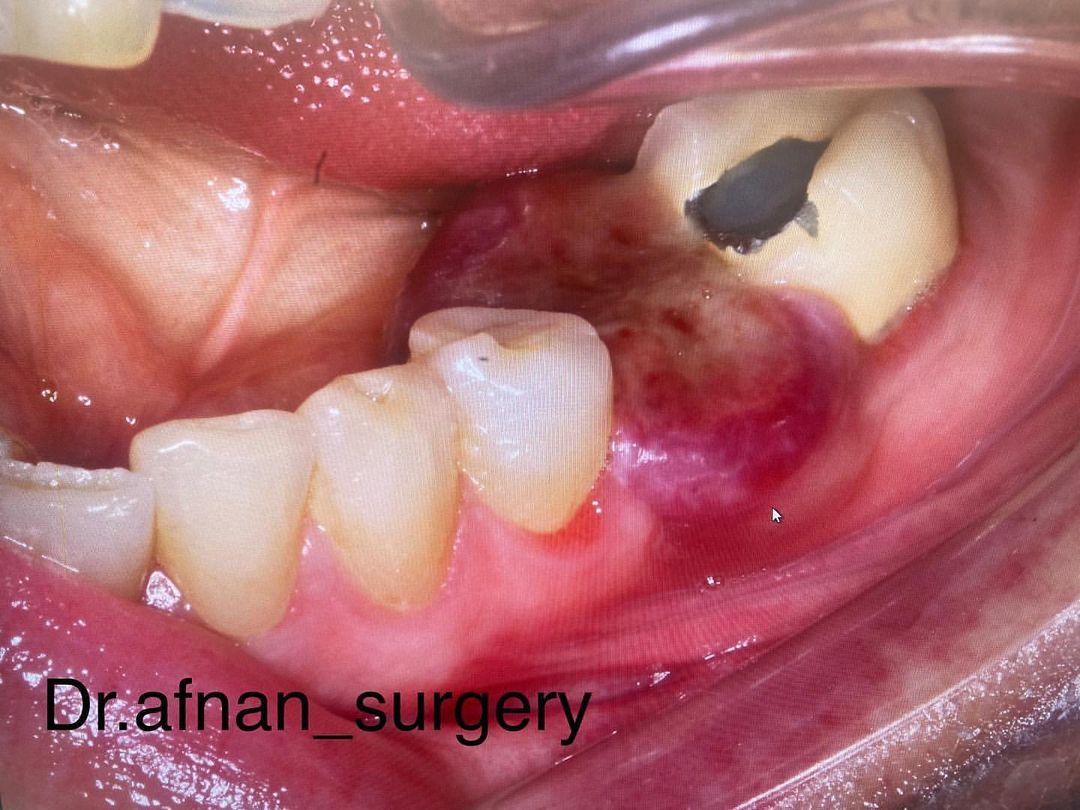

Female patient: 55 years old

A couple months ago she started to get this change in her mouth. It’s not painful, but is quite uncomfortable. She tells us that at the beginning it was a little change, but slowly it has grown to this size.

Symptom: pain if she chews the food on this side.

Only in the keratinized gingiva. About 1,5cm. Starts from the buccal keratinized gingiva and stretches lingual. Strongly elvated. Ulceration. The gingiva is exophytic all the way and sessile. Bleeding on probing.

X-ray: Normal. No reaction in the bone or adjacent teeth.

What do you think this is?

Hint: Hybrid lesion.